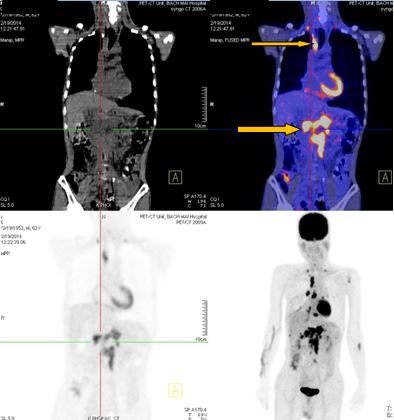

-          Bệnh nhân đã được tiến hành chụp PET/ CT đánh giá, kết quả:

+ Vùng phế quản gốc phải có khối KT 2,4x1,7cm, tăng hấp thu F-18 FDG, max SUV=8,50. Hạch trung thất kích thước lớn nhất 3,1x3,5cm, max SUV=10,29

+ Hạch thượng đòn phải KT 1,1cm, tăng hấp thu F-18 FDG, max SUV=5,67; Hạch thượng đòn trái KT 0,8cm, max SUV=3,97. Tổn thương cung sau xương sườn số 2 bên phải tăng hấp thu F-18 FDG, max SUV=3,13.

+ Nhiều hạch ổ bụng dọc theo ĐM chủ bụng tạo thành khối lớn KT 8,5x5,1 cm và 5,1x3,9cm, tăng hấp thu F-18 FDG, max SUV=10,45. Nhu mô gan hạ phân thùy VI có nốt KT 1,2cm, tăng hấp thu F-18 FDG, max SUV=4,15.

- Trước điều trị: Khối u 2,4x1,7cm, max SUV=8,50. Hạch dưới carina KT 3,1x3,5cm, max SUV=10,29

- Sau điều trị 4 thángKhông rõ u, không có hạch trung thất

-Trước điều trị: Nhiều hạch ổ bụng dọc theo ĐM chủ bụng tạo thành khối lớn KT 8,5x5,1 cm và 5,1x3,9cm,  max SUV=10,45.

-Sau điều trị 4 tháng: Không có hạch ổ bụng